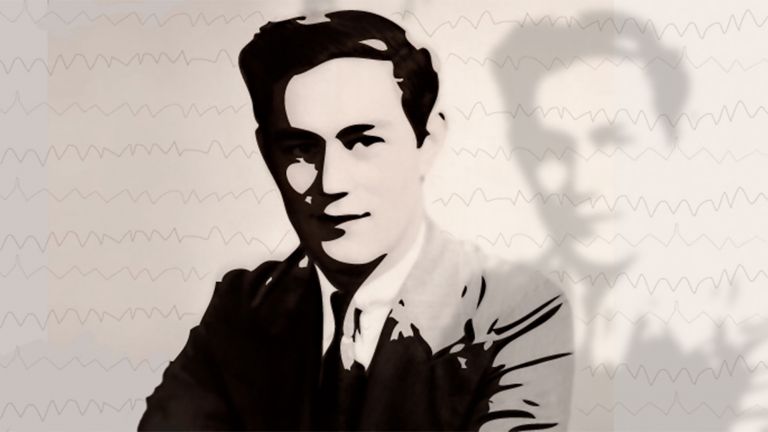

Durch eine Operation verlor der Amerikaner Henry Molaison die Fähigkeit, neue Erinnerungen zu formen – und die Hirnforschung gewann ihren berühmtesten Patienten.

- Einer der berühmtesten Patienten der Hirnforschung ist Henry Gustav Molaison, bekannt unter seinen Initialien HM als „Der Mann ohne Gedächtnis“.

Am 1. September 1953, im Alter von 27 Jahren, wurde Henry Gustav Molaison im Krankenhaus von Hartford in Connecticut betäubt. Dann bohrte der Neurochirurg Wilbur Beecher Scoville zwei Löcher in den Schädel seines Patienten und entfernte auf beiden Seiten des Gehirns ein Stück des Schläfenlappens. Es war eine Operation, die Molaison weltberühmt machen sollte, weil er damit sein Gedächtnis und seine Identität verlor.

Als Scoville und die kanadische Psychologin Brenda Milner ihre Beobachtungen zu Molaison 1957 im Fachblatt „Journal of Neurology, Neurosurgery and Psychiatry“ veröffentlichten, wurde er zum „Fall H.M.“ – und zu einem der berühmtesten und wichtigsten Studienobjekte in der Geschichte der Psychologie. Die Arbeit ist in der Fachliteratur hundertfach zitiert worden und wird es heute noch. „Das ist wirklich ein Meilenstein gewesen“, sagt Hans Markowitsch, Neuropsychologe an der Universität Bielefeld (inzwischen emeritiert).

Dass H.M.s Verletzung Wissenschaftlern so geholfen hat, das Gedächtnis besser zu verstehen, scheint H.M. ein Trost gewesen zu sein. „Was Scoville über mich gelernt hat, das hat auch anderen Menschen geholfen – und darüber bin ich froh“, habe er einmal gesagt, schreibt Corkin. Überhaupt sei er ein sehr angenehmer Mensch gewesen. „Er war freundlich und hatte einen guten Sinn für Humor.“ Obwohl H.M. sie über Jahrzehnte immer und immer wieder sah, hatte er höchstens ein vages Gefühl, sie zu kennen. „Manchmal sagte er, ich käme ihm bekannt vor, so als sei ich mit ihm zur Schule gegangen“, sagte Corkin.

Molaison starb am 2. Dezember 2008 in einem Altersheim in Connecticut. Sein Leichnam wurde sofort ins Massachusetts General Hospital in Charlestown gebracht, wo Forscher unter anderem des Brain Observatory in San Diego die Nacht durcharbeiteten, um Gehirnscans anzufertigen und H.M.s Gehirn für die Nachwelt zu erhalten. Henry Molaison selbst konnte keine neuen Erinnerungen mehr formen, aber in der Welt der Wissenschaft hat er bleibende Spuren hinterlassen.